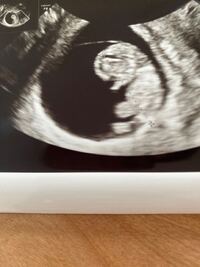

Nov 12, 19 · 妊娠すると「赤ちゃんの身長や体重は正常かな?」と発育の具合が気になってきますよね。出産に向けて定期的に妊婦健診を受ける中で、「赤ちゃんの頭がちょっと大きいかも」と医師から言われたりすると、心配になるかもしれません。今回は胎児の頭が大きいときの原因や、出産時にマダムまかろんさんの妊娠9週目のエコー写真 胎児の姿が見えてきた! エコー画像で頭と胴体が分かれた人間らしい姿を見て、いよいよ妊娠したという実感がわいてきました。 それと同時に、このまま無事に育ってくれるのだろうかという不安で毎日祈るJul 03, 13 · 胎児の頭だけが大きい? 初めまして29wの妊婦です。エコーで気になる事があるので相談させてください。エコーで測るといつも頭だけが1w~2wと大きめです。私も頭が大きめなので私の遺伝かなー♪と思ってたのですがネットでなにげなく調べたら水頭症やらダウン症やらとでてきて不安